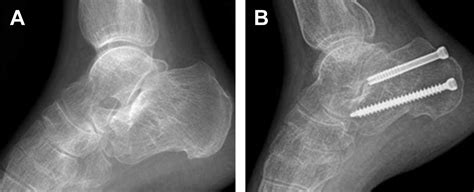

Fractures of the calcaneus are common and account for approximately 60% of tarsal injuries. A series of four patients with tongue type calcaneal fractures were treated using a hurricane strap technique.

The secondary fracture line directly extends in a posterior direction, producing a large superior, posterior, and lateral fragment, with the. The final outcome often depends on the severity of the initial injury. It is a rare type of fracture but has potentially debilitating results.

The goal of calcaneal fracture orif is to place the bones back to their original position prior to the injury. No cast required, and motion is performed immediately. Axial plane beneath the posterior facet exiting posteriorly. Percutaneous and open reduction techniques can aid in treating this injury. Tongue type fractures should be splinted in 30 degrees of planarflexion to relieve soft tissue tension. Note loss of the crucial angle of gissane. Fractures of the calcaneus are common and account for approximately 60% of tarsal injuries. The final outcome often depends on the severity of the initial injury. A calcaneal fracture is a break of the calcaneus (heel bone). Fractures of the calcaneus comprise approximately 2% of all fractures and 60% of tarsal fractures 1. They result from an axial load and may demonstrate patients will present with pain and swelling, with the inability to bear weight. Bilateral fractures of the calcaneus occur approximately 10% of the time. Tongue type calcaneal fracture radiology. A calcaneus fracture is a heel bone fracture. During this procedure, the surgeon stabilizes the bone with hardware to allow the bone to heal properly. It is a rare type of fracture but has potentially debilitating results. Primary fracture line runs obliquely through the posterior facet forming two fragments, the secondary fracture line runs in one of two planes the axial plane beneath the facet exiting posteriorly.